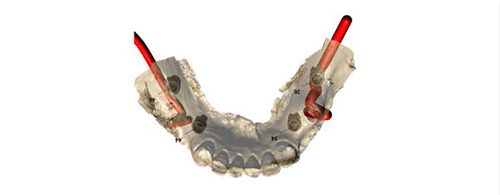

CTデータをもとに三次元的なシミュレーションを行い、補綴主導で埋入ポジションを設計したうえで、専用のサージカルガイドを作製します。

このガイドを実際の手術時に使用することで、術前に立てた埋入位置・角度・深度をより高い精度で再現することが可能となります。